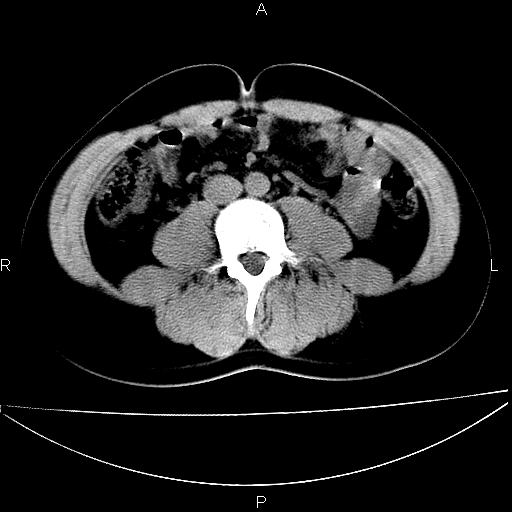

标题: CT29462:双测输尿管扩张

男 25岁 自述 尿频尿急,排尿困难20多天.无腰痛, b超说左肾盂轻度积水,左输尿管上端扩张.未见结石影. ct我看双侧肾盂轻度积水,双输尿管上端都扩张,大家看看能看见结石吗?

双肾轻度积水,双侧输尿管上段扩张(原因待查)。

双输尿管扩张下端未见高密度结石和输尿管晕轮征,不好说是结石.增强后如何?

双肾轻度积水,未见明确结石,薄层对结石检出率较高。

双肾盂及双输尿上段轻度积水,双输尿管未见明显结石影。